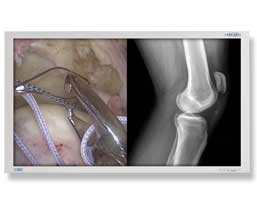

GTI Groups offers permanent solutions in medical industry and we only work with the global leaders in designing and manufacturing comprehensive radiology and medical imaging and informatics solutions for today’s operative process. Our partners’ market leadership is built upon their unique ability to supply the medical profession with technologies that enable practitioners to integrate information from many sources, visualize a defect or condition within the body and to perform an intervention that improves the quality of care. They dominate today’s surgical markets and are considered the industry standards for the digital world. So we always feel a little bit lucky for finding out the right partners and right products.

Our Medical Imaging Professional Services provides a range of services and analytical tools to supplement our solutions and are designed to help you and your organization realize the full value of medical imaging in your facilities. RIS (radiology information) and CVIS (cardiovascular imaging systems) are designed to help health care organizations of all sizes and complexity manage the massive amount of specialized imaging applications that come from dealing with today’s medical imaging departments. According to the Medical Imaging Monitors, we are pretty experienced and have a great knowledge upon the industry. Our business partners are as follows: